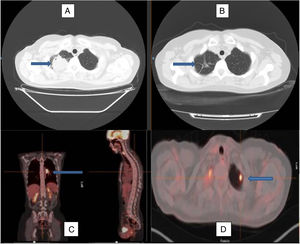

Imagen de tomografía axial computarizada al diagnóstico (A) y tras el tratamiento con corticoides (B), observándose la remisión de la lesión en el lóbulo superior derecho, permaneciendo en su localización algunos tractos fibrosos residuales (flechas). Imagen de PET-TAC con imagen hipercaptante en el hilio pulmonar izquierdo (C) y en el lóbulo superior izquierdo (D), marcadas por las flechas, que reflejan la afectación multilocular del caso.

Se presenta el caso de una mujer de 49 años, exfumadora, con un índice de consumo acumulado de 2 paquetes/año, con antecedentes personales de hipotiroidismo. Como tratamiento habitual tenía levotiroxina de 75mcg, un comprimido al día. Acudió a urgencias hospitalarias por un cuadro de cefalea tras un episodio de sinusitis, sin clínica respiratoria asociada, donde en el estudio complementario básico se incluyó una radiografía simple de tórax, en la que se visualizó una lesión apical derecha de contornos irregulares, como hallazgo incidental. Se solicitó una primera tomografía axial computarizada que fue informada como «masa tumoral redondeada en el vértice pulmonar derecho, de contornos irregulares, lobulados y con espiculaciones hacia el parénquima circundante. La lesión presenta un realce heterogéneo con el contraste, contactando ampliamente con la pleura apical posterior y superior, con un tamaño aproximado de unos 45×42mm, sin evidencia de extensión o infiltración pleural o extrapleural; en el vértice pulmonar izquierdo se visualiza una pequeña imagen nodular subcentimétrica, subpleural, de dudosa significación». Ante este hallazgo se realizó una tomografía por emisión de positrones donde se destacó la presencia de dicha masa, metabólicamente activa, con un valor de consumo entandarizado máximo (SUVmáx) de 27,5, y la observada en el lóbulo superior izquierdo con un SUVmáx de 7,5. A nivel mediastínico se informó de adenopatías hiliares bilaterales, destacando un conglomerado hiliar izquierdo de 3,2×2,1×4,1cm con un SUVmáx de 14,1 (fig. 1). Ante la alta sospecha de malignidad se decidió la realización de una biopsia con aguja gruesa de la lesión mayor, cuyo resultado mostró la presencia de fibrosis e infiltrado linfohistiocitario polimorfo sugestivo de proceso inflamatorio o pseudotumor inflamatorio con estudio molecular negativo para mutaciones del gen EGFR. No se realizó estudio para el gen ALK. Los marcadores tumorales (CEA, CA 15.3, CA 19.9, CYFRA-21, Ag de células escamosas, Pro-GAP y enolasa) fueron negativos. No presentó anemia ni trombocitosis. Tras este resultado se estimó necesaria la confirmación mediante la realización de una nueva biopsia con aguja gruesa, cuyo diagnóstico fue similar y la realización de una fibrobroncoscopia, en la que se visualizó una mucosa engrosada de aspecto inflamatorio en el lóbulo inferior izquierdo, de donde se realizó cepillado bronquial a ciegas sin obtención de células neoplásicas. Ante la ausencia de datos de malignidad y la existencia de varias lesiones que dificultaban el abordaje quirúrgico, se acordó el inicio de tratamiento con deflazacor a dosis de 1mg/kg de peso al día durante 2 meses, reduciéndose a la mitad los siguientes 2 meses y suspendiéndose al mes siguiente. Se realizaron 3 estudios de tomografía axial computarizada durante el tratamiento, observándose una disminución progresiva del tamaño tumoral, así como la presencia de tractos lineales fibrótico-cicatriciales y bronquiectasias por tracción en la zona, con desaparición del nódulo contralateral.